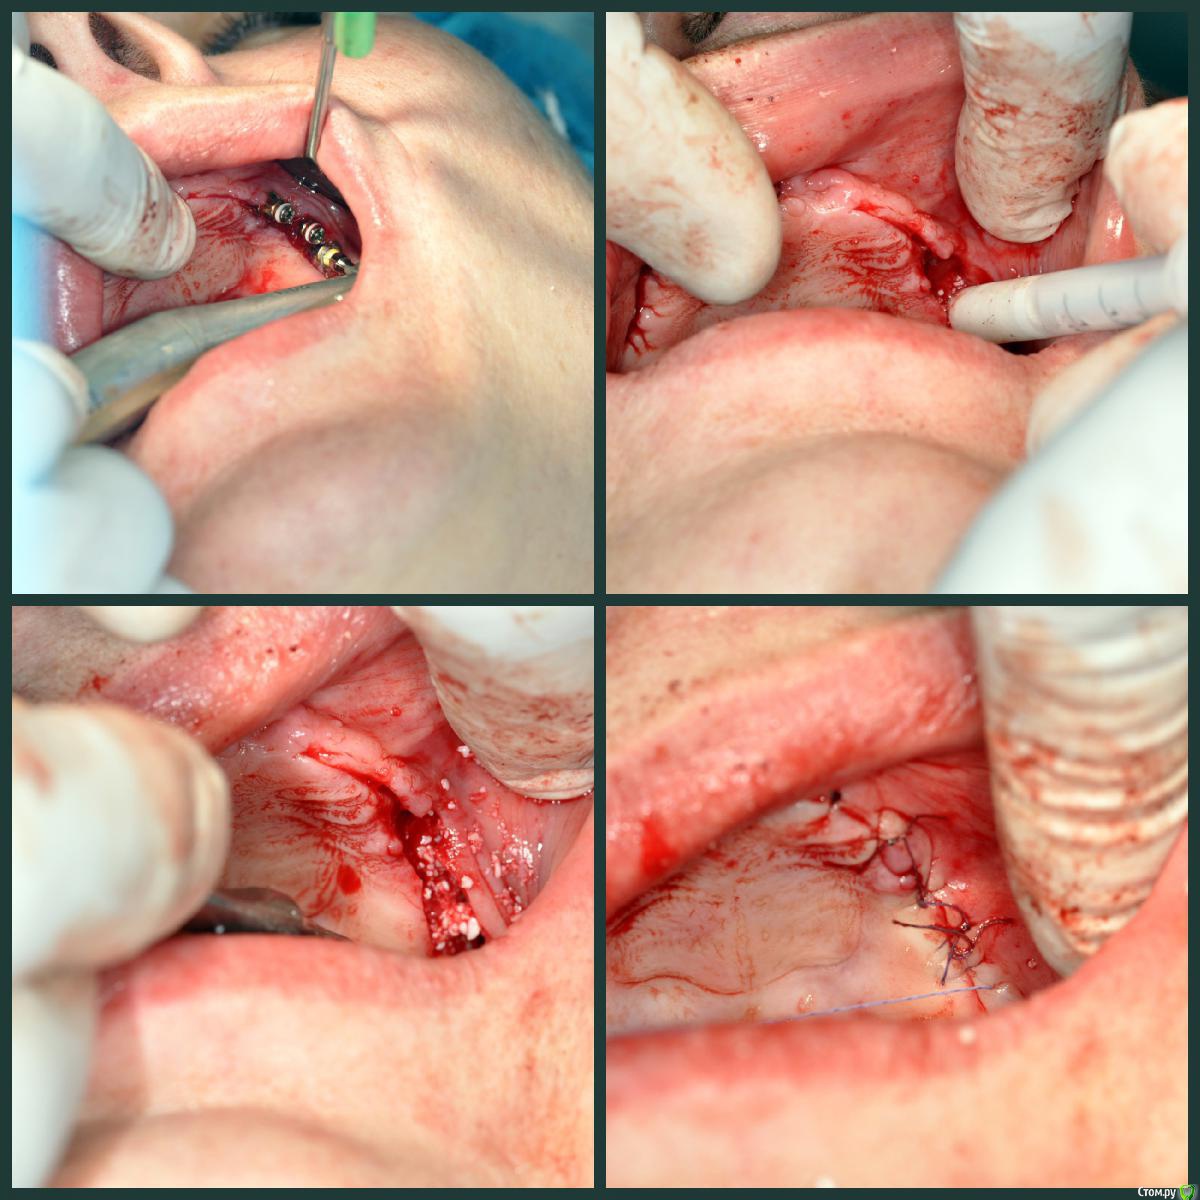

Сергей Таранов Опубликовано 28 ноября, 2016 Поделиться Опубликовано 28 ноября, 2016 Хронический периодонтит, фрактура корней 11,15,21,24. Удалены R 11,15,21,24. Проведена имплантация ВЧ в области 13-16, 23-26 с одномоментным открытым синус-лифтингом с использованием остеотропного материала mp3 (OsteoBiol by Tecnoss). Через 5 месяцев проведено протезирование на имплантах. 4 Ссылка на комментарий

Сергей Таранов Опубликовано 29 ноября, 2016 Автор Поделиться Опубликовано 29 ноября, 2016 Это стандартные имплатны системы Осстем 9,5-11 мм Ссылка на комментарий

krokomot Опубликовано 29 ноября, 2016 Поделиться Опубликовано 29 ноября, 2016 у стандартной платформы же зеленые имплантоводы и желтые у мини 1 Ссылка на комментарий